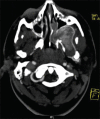

Juvenile nasopharyngeal angiofibroma (JNA) is a rare benign tumor arising predominantly in the nasopharynx of adolescent males. It is an aggressive neoplasm and shows a propensity for destructive local spread often extending to the base of the skull and into the cranium. Clinically, however, it is obscure with painless, progressive unilateral nasal obstruction being the common presenting symptom with or without epistaxis and rhinorrhea. Diagnosis of JNA is made by complete history, clinical examination, radiography, nasal endoscopy and by using specialized imaging techniques such as arteriography, computer tomography and magnetic resonance imaging. Histopathology reveals a fibrocellular stroma with spindle cells and haphazard arrangement of collagen interspersed with an irregular vascular pattern. A case report of JNA with rare intra-oral manifestation in a 17-year-old male patient is presented in the article. JNA being an aggressive tumor may recur posttreatment. Thus, early diagnosis, accurate staging, and adequate treatment are essential in the management of this lesion.